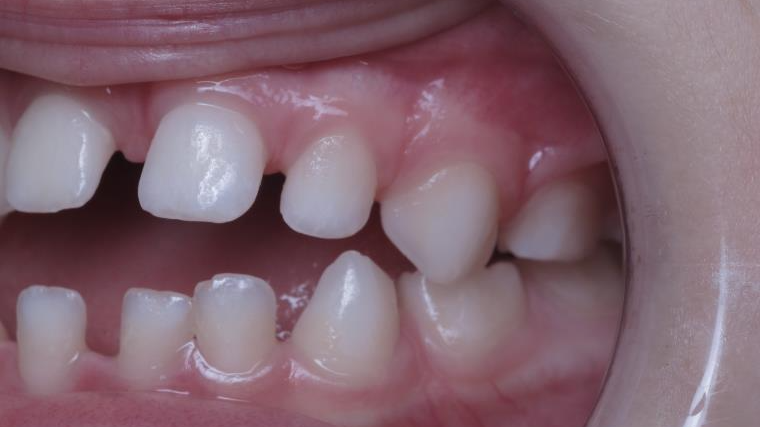

appareillage mobile pendant 3 ans

surveillance évolution de la dentition

bilan de début et en cours de traitement